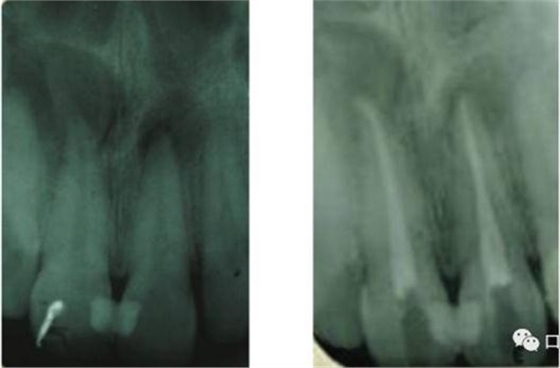

41 治療前X光片

46治療前X光片